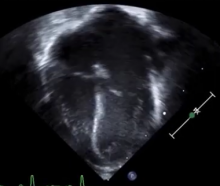

A follow-up echocardiogram two weeks later showed a multilobed right ventricular pseudoaneurysm, measuring at its mouth 11 millimeters. To-fro flow was seen without any thrombus formation and a mild to moderate pericardial effusion. This was confirmed with CT.